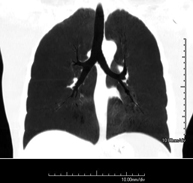

- Tórax- TC Tórax Prueba diagnóstica que consiste en obtener imágenes del tórax de alta definición anatómica (pulmones, corazón, mediastino, grandes vasos, caja torácica, etc.) mediante el empleo de un equipo de TC (Tomografía Computarizada). Dichas imágenes se estudian posteriormente en una estación de trabajo que permite reconstrucciones bidimendionales en diferentes planos del espacio y también reconstrucciones 3D (volumétricas). Algunos estudios requieren el empleo de contraste yodado para mejorar la definición de las imágenes. Prueba diagnóstica que consiste en obtener imágenes del tórax de alta definición anatómica (pulmones, corazón, mediastino, grandes vasos, caja torácica, etc.) mediante el empleo de un equipo de TC (Tomografía Computarizada). Dichas imágenes se estudian posteriormente en una estación de trabajo que permite reconstrucciones bidimendionales en diferentes planos del espacio y también reconstrucciones 3D (volumétricas). Algunos estudios requieren el empleo de contraste yodado para mejorar la definición de las imágenes.

- TC Tórax alta resolución Prueba diagnóstica que consiste en el estudio del pulmón mediante el empleo de un equipo de TC (Tomografía Computarizada) obteniendo imágenes bi y tridimensionales que permiten un estudio anatómico altamente específico del pulmón, pudiendo valorar estructuras anatómicas de tamaño muy pequeño. Es una técnica muy importante en el estudio de los pacientes con sospecha de enfermedad pulmonar. Prueba diagnóstica que consiste en el estudio del pulmón mediante el empleo de un equipo de TC (Tomografía Computarizada) obteniendo imágenes bi y tridimensionales que permiten un estudio anatómico altamente específico del pulmón, pudiendo valorar estructuras anatómicas de tamaño muy pequeño. Es una técnica muy importante en el estudio de los pacientes con sospecha de enfermedad pulmonar.